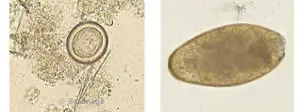

Parasitoses alimentaires

Présentation synthétique des parasites et parasitoses alimentaires